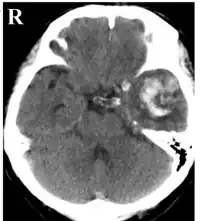

CT scan showing cerebral contusions, hemorrhage within the hemispheres, subdural hematoma on the left, and skull fractures[1]